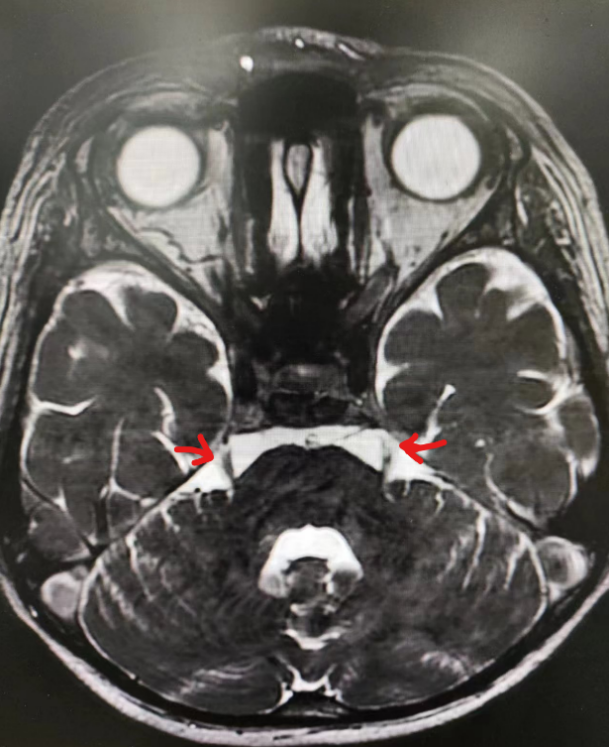

术前磁共振影像排除继发性疼痛,术中透视见穿刺针穿刺位置良好。